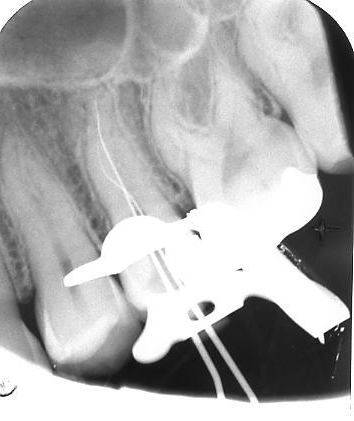

Bij de endodontische behandeling wil een dikkere vijl  niet verder dan tot de wortelsplitsing. Bij goed manipuleren met iets voorgebogen dunnere handvijlen lukt het dan vaak wel om één van de kanalen toegankelijk en doorgankelijk te maken. Meer problemen geven dan de andere kanalen na de splitsing. De behandelmicroscoop maakt het preparen van dergelijke kanalen een stuk gemakkelijker omdat de verschillende kanalen ter plaatse van de splitsing zichtbaar zijn te maken. Ook het vullen van diepe kanalen is een stuk eenvoudiger als men de beschikking heeft over een behandelmicroscoop.